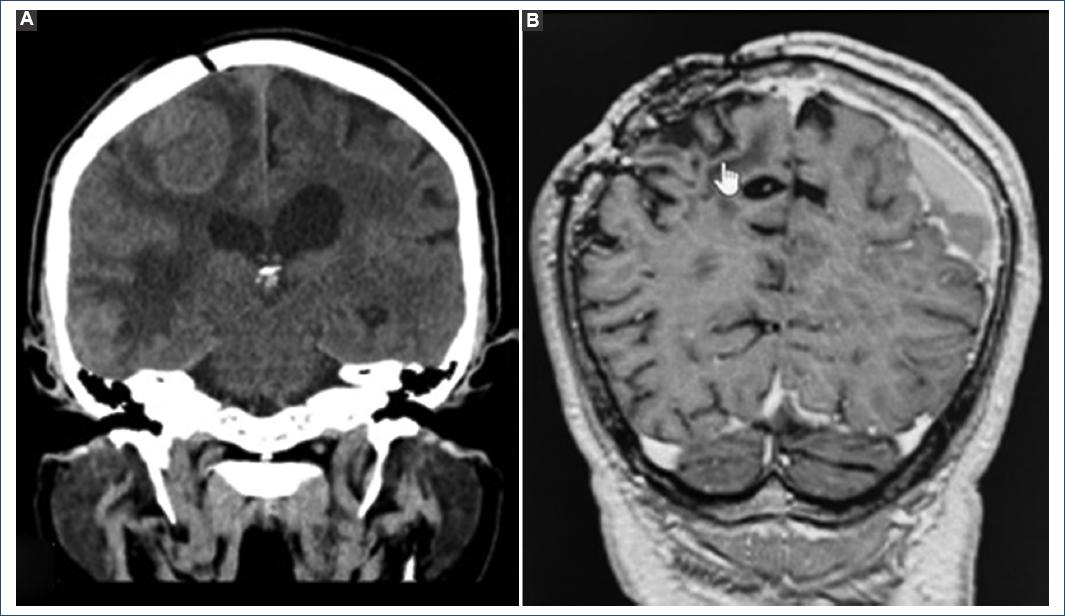

Three months after the first intervention, the patient presented left hemiparesis again and seizures of focal onset that were secondarily generalized, so phenytoin 100 mg every 8 h was added to the treatment. Neuroimaging was performed again, identifying tumor recurrence of the right frontoparietal lesion and growth of the right temporal metastasis, which requires a second surgical procedure and subsequently fractionated radiosurgery with a linear accelerator treating 5 lesions at a dose of 18 GY using modulated volumetric arctherapy (Fig. 3).

Figure 3 A: simple computed axial tomography in coronal section, tumor recurrence of right frontoparietal lesion, and perilesional vasogenic edema 3 months after intervention. B: post-operative magnetic nuclear resonance of the second intervention in the T1 sequence coronal section, total resection of the right frontoparietal lesion.